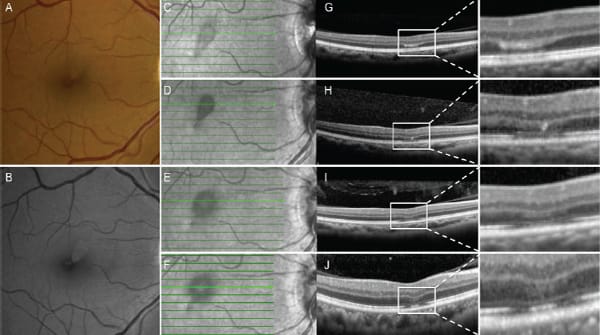

While the clinical examination findings in AMN are often quite subtle, near-infrared (NIR) reflectance imaging usually shows characteristic dark gray, paracentral lesions, which typically point toward the foveal center (Figure 2C).11,18-20 As this condition progresses, these gray hyporeflective lesions can increase in intensity (Figure 2D) and can extend laterally (Figure 2E), before eventually fading (Figure 2F).

Recently, authors have reported that AMN lesions may develop at the OPL/ONL junction with associated outer macular disruption.11,18 Fawzi et al.11 performed complex multimodal imaging of patients with AMN, demonstrating acute paracentral band-like hyper-reflective plaques at the ONL/OPL junction on SD-OCT (Figure 2G), indicating disruption of photoreceptor cell bodies and their axons.

With resolution of this ONL/OPL hyper-reflectivity, thinning of the ONL was noted. Changes developed in the outer segments of the photoreceptors and their junction with the RPE, including disruption of the ellipsoid and interdigitation zones and thinning of the photoreceptor outer segments (Figures 2H and 2I).

Figure 2. Baseline color fundus (A) and red-free (B) images demonstrating a superficial, hyporeflective, wedge-shaped retinal lesion superonasal to the fovea in the right eye of a patient with AMN. Baseli e near-infrared (NIR) reflectance image (C) showing a gray teardrop-shaped lesion with corresponding spectral-domain OCT (G), demonstrating a band-like hyper-reflective lesion at the level of the outer plexiform layer with an intact ellipsoid zone and early disruption of interdigitation zone. Two-week follow-up NIR reflectance with increased intensity of the teardrop lesion (D) and corresponding SD-OCT (H) showing resolution of the hyper-reflective lesion at OPL and thinning of the outer nuclear layer (ONL) and ellipsoid zone and interdigitation zone disruption. One-month followup NIR reflectance with lateral extension of the teardrop lesion (E) and SD-OCT (I) with a corresponding spread of interdigitation zone disruption. Six-week follow-up NIR reflectance with a persistent teardrop lesion (F) and corresponding SD-OCT (J) revealed the reconstitution of the ellipsoid zone and persistent thinning of the ONL and outer segments.

Thinning of the ONL and disruption of the interdigitation zone persisted even after normalization of the ellipsoid zone (Figure 2J), an important finding differentiating AMN from MEWDS, in which outer segment abnormalities on OCT typically normalize completely after the acute episode.23